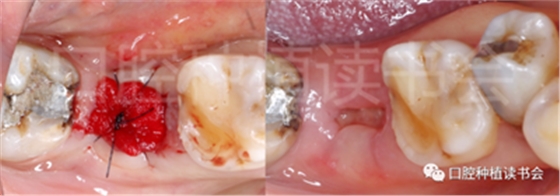

圖1 無法保留的上頜隱裂后牙,拔牙后即刻種植。

后牙區(qū)或者是非美學區(qū)即刻種植,對于患者和臨床醫(yī)生而言,存在一些明顯的優(yōu)勢;比如更小的外科創(chuàng)傷、更短的愈合周期、更少的椅旁時間、更高的患者接受度以及更低的治療費用等。除此之外,在上頜后牙區(qū)即刻種植還可以減少上頜竇的氣化現(xiàn)象【Sharan等.2008】;但并非所有的后牙位點都適合即刻種植,后牙區(qū)即刻種植對醫(yī)生的技術和經(jīng)驗要求更高;由于解剖等諸多條件的差異,美學區(qū)即刻種植的臨床注意事項與后牙區(qū)即刻種植存在諸多不同之處;與本文旨在通過詳細的文獻回顧及臨床案例對后牙區(qū)即刻種植治療提供臨床參考。